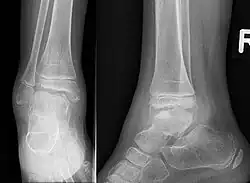

Trevor disease in a nine-year-old girl: talus

3D CT image of Trevor's disease of the ankle and talus.

This disorder is rare, and is characterised by an asymmetrical limb deformity due to localized overgrowth of cartilage, histologically resembling osteochondroma. It is believed to affect the limb bud in early fetal life. The condition occurs mostly in the ankle or knee region and it is always confined to a single limb. This usually involves only the lower extremities and on medial side of the epiphysis. It is named after researcher David Trevor.[1]